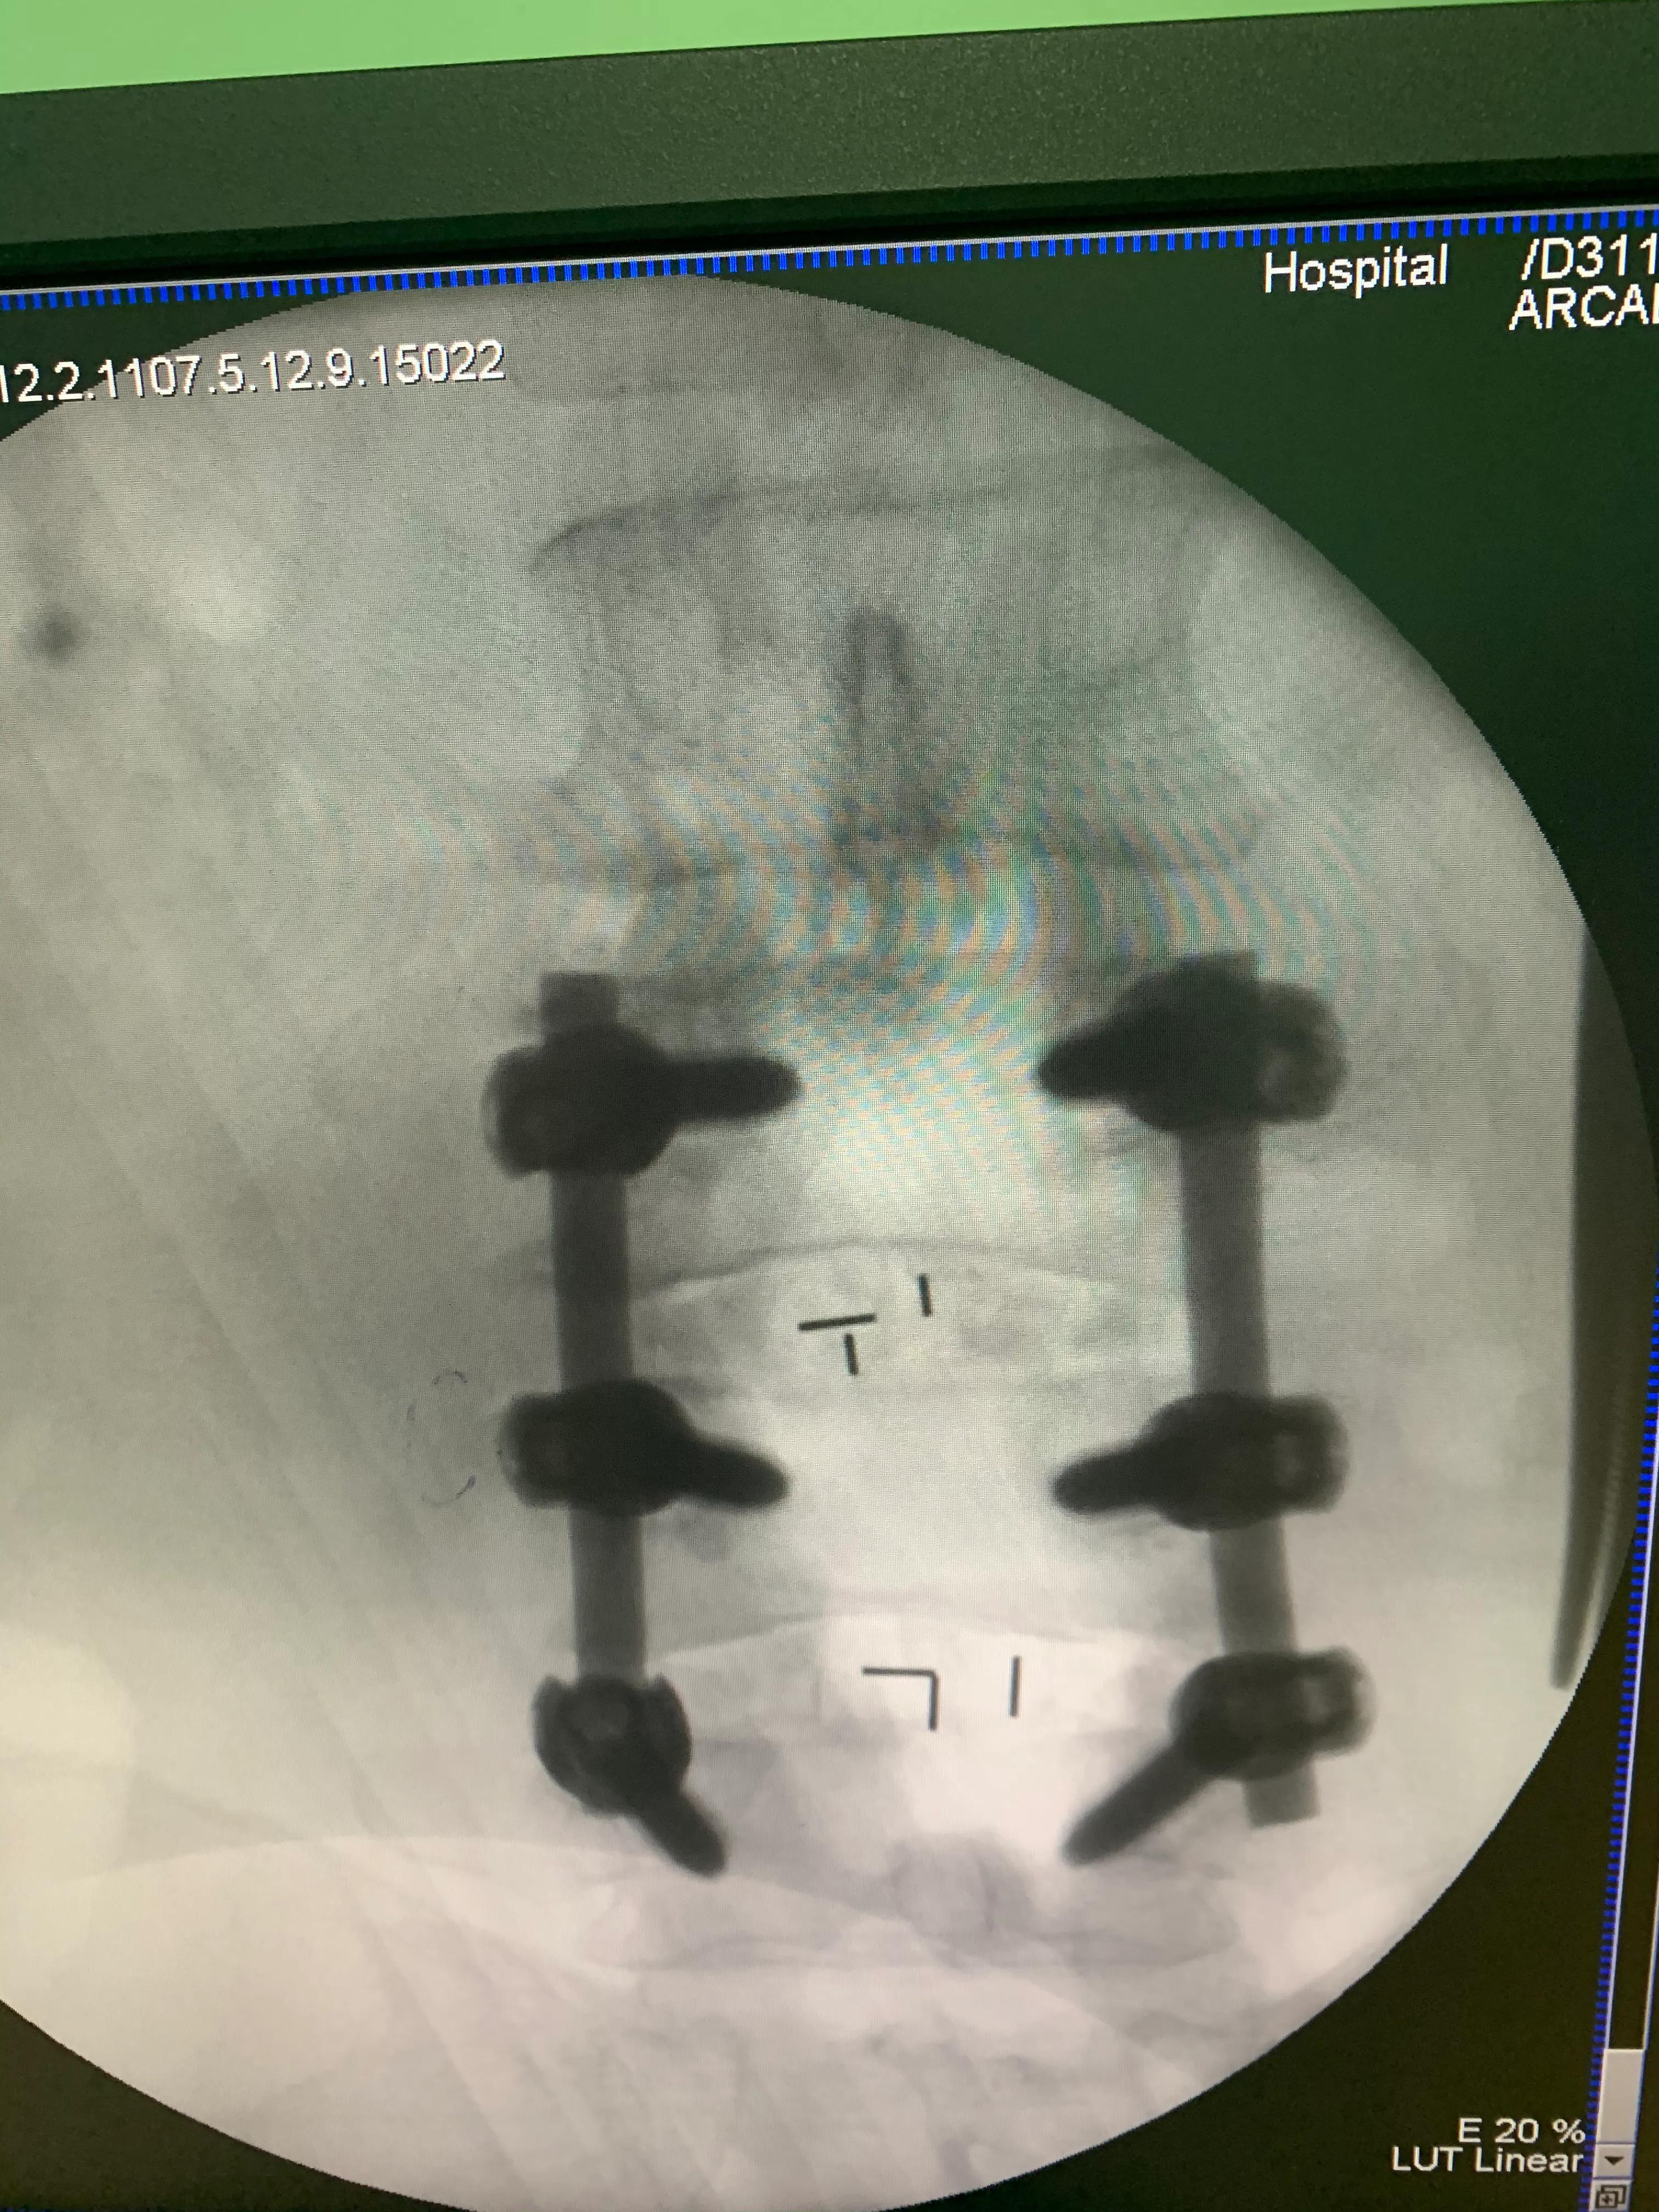

椎间盘切除术 椎间盘切除术就是通过手术方式把椎间盘切除。这是腰椎间盘突出症最经典的手术。不过别误会,椎间盘切除并不等于把整个椎间盘都给摘了,而只是切除那些突出或脱出的,并压迫脊神经的椎间盘组织,简单讲,就是摘了髓核,保留纤维环。所以,这种术式又称为髓核摘除术。这种手术创伤小,并发症少,对人体影响小,由于只切除部分椎间盘,因此有复发的可能。不过,如果严格掌握手术的适应证,复发率非常低。单纯髓核摘除术,又叫小开窗治疗,通常,在腰后方正中位置做切口,然后在病变椎间盘对应的椎板上做一个小洞(直径约1 厘米),再让器械穿过这个小洞,将髓核取出来。这一手术的皮肤切口,一般在5~10 厘米。有时,由于是双侧椎间盘突出,或有巨大的椎间盘突出等问题,医生为了能有更好的手术视野及更好地为神经减压会先切除半椎板或者全椎板。这就相当于,原来只需在椎板上开一个小窗户,现在需开一个“大椎间盘切除术:给神经减减压窗户”,甚至把墙推掉,直接做个“落地窗”。 内固定融合术 椎体内固定融合术,也就是常说的“打钉”。椎间盘切除后,虽然能有效缓解疼痛,但毕竟是缺了椎间盘,时间久了,椎间隙会慢慢变窄,引起神经根管狭窄,同时腰椎前部的结构应力也会进一步下降,后部结构应力上升,造成腰椎不稳。而本来是32 个椎间盘兄弟齐心协力撑起脊柱,如今有人不幸“夭折”,剩下的,特别是它相邻部位的椎间盘承受的载荷就会显著增加,从而加重腰椎不稳,可以引起严重的腰痛症状。为避免术后复发,有些医生就会选择给患者做融合术。将椎间盘全部切除,然后,在两个椎体间植入骨头,来维持椎间隙的高度。由于异体骨(即别人的骨头)比较难愈合,所以选用的骨头一般取于本人的髂骨。髂骨也就是髋骨上的一部分。目前,有PEEK 材料的椎间融合器,可以用术中咬除的椎板碎骨填塞后椎骨,避免再凿取自体髂骨。由于骨头愈合需要较长时间,为了使患者能早期下床活动,目前,多在植骨后采用钢钉进行固定,因此内固定融合术又被俗称为“打钉”。